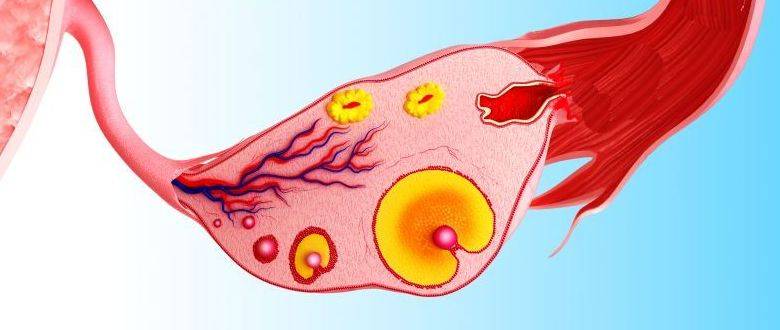

Созревание фолликула в яичнике: этапы и процессы